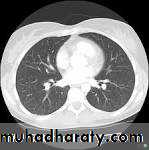

Application:

Suited for bone injuries, Lung and Chest imaging, cancer detection

Computed Tomography (CT)-Chest

8 mSv3 years